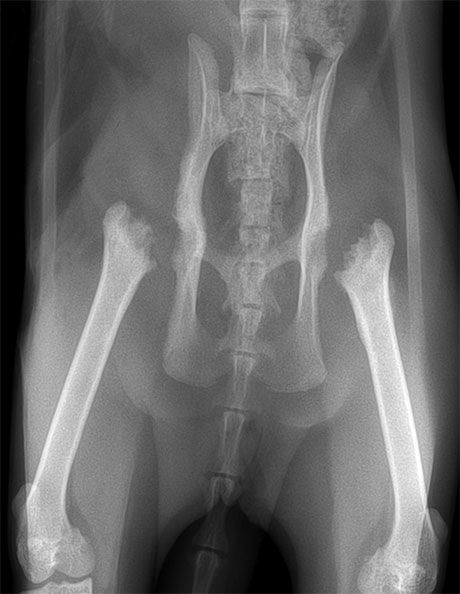

Bei diesem 10 jährigen Labrador ist die HD stark ausgeprägt. Der linke Hüftkopf ist aus der Pfanne luxiert, starke Arthrose hat sich gebildet. Neben der Schmerzen kann das Bein nicht nach hinten gestreckt werden, da der Hüftkopf am Becken anstösst.

Femurkopfresektion

Weil eine Hüftprothese aus verschiedenen Gründen nicht in Frage kam, haben wir den luxierten Hüftkopf entfernt (Femurkopfresektion). Die Muskulatur und Bindegewebe bilden ein funktionierendes "Pseudogelenk" aus. Dadurch hat der Hund deutlich weniger Schmerzen und gewinnt Lebensuqalität. Diese Operation wird normalerweise eher bei kleinen Hunden oder Katzen gemacht, funktioniert aber auch bei grösseren Tieren, wenn eine Hüftprothese nicht möglich ist.